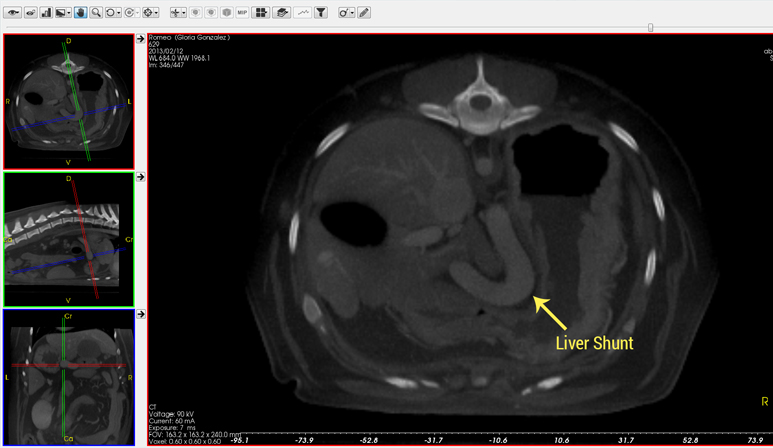

Liver Shunt – Congenital or Acquired Condition

- A portosystemic shunt (PSS), also known as a liver shunt, is not necessarily that common in dogs, but in certain breeds (Yorkies, Jack Russell Terriers, Cocker Spaniels, Lhasa Apsos, Poodles, Labs) they are more common. If your dog develops liver disease it may have a liver shunt. If your puppy begins acting strangely (staring into space, acting disoriented, circling or head pressing, having seizures) a liver shunt is something that needs to be investigated and potentially may be surgically corrected. These patients may or may not have elevated liver enzymes but almost always have an elevated bile acids test. If your pet has elevated bile acids, a CT scan is the ideal imaging tool to evaluate the liver and identify any possible liver shunts (abnormal vessel). CT scans are superior to an ultrasound when evaluating for liver shunts.

One of the most common indications for which we perform abdominal CT scans is to evaluate for the presence of a portosystemic shunt (PSS) or liver shunt- such as the one shown here.